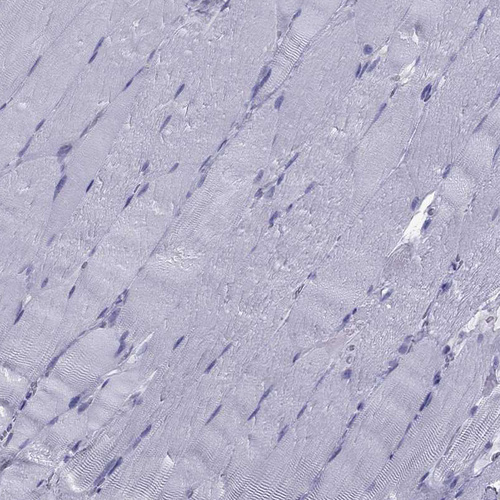

Immunohistochemistry analysis in human colon and skeletal muscle tissues using HPA035464 antibody. Corresponding TFF3 RNA-seq data are presented for the same tissues.